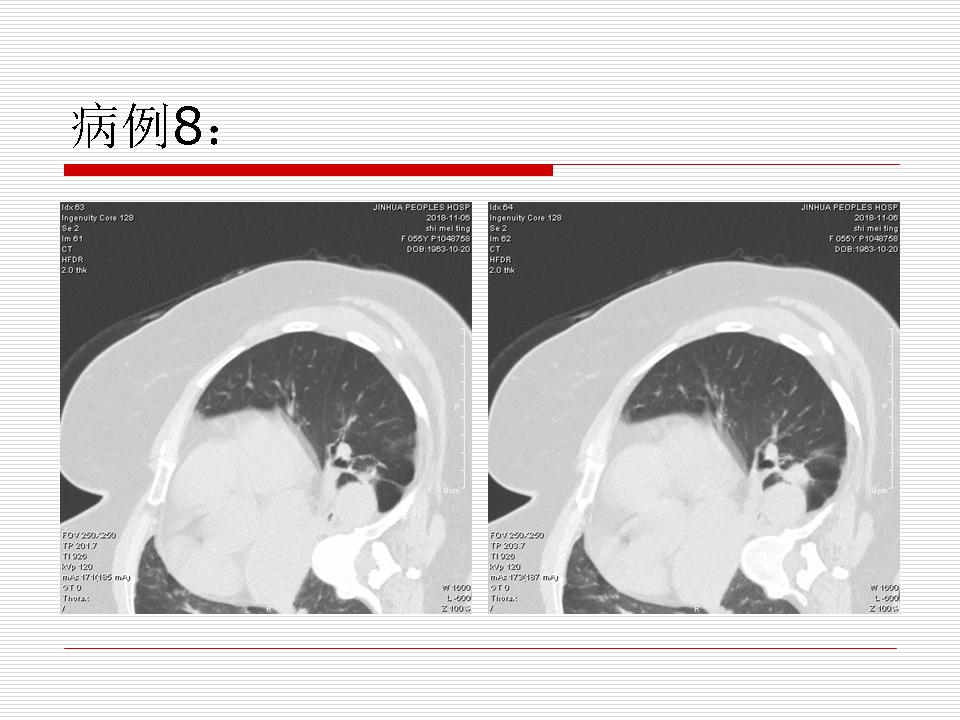

肺部阴影永恒且最重需要鉴别的是:到底是炎症还是肿瘤?但临床的病例中的影像表现难以界定或有些肿瘤特征,同时又有些炎症特点是非常常见的情况。作为临床医生我们怎么去总结分析,并找到之所以是炎症或之所以是肿瘤的细微差别或特点非常重要,也非常有用。2019.12.7浙江省2019年胸心外科学学术年会在宁波召开时,我的临床病例分析与经验总结<那些像肺癌的炎症与像炎症的肺癌>获得在大会交流的机会,以下为该PPT的内容,与你分享,希望对同道有益,有借鉴与启迪。若有探讨与进一不完善的建议,欢迎文末留言讨论: